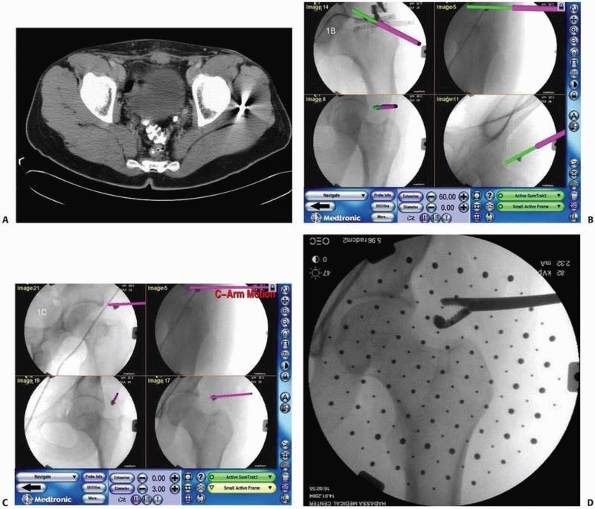

CT images during surgery when necessary.9,12 Figure 17-8 shows an example of navigation with 3D fluoroscopy.

![]() |

|

FIGURE 17-8

Pedicle screw insertion with three-dimensional fluoroscopy. Screen view of three-dimensional fluoroscopy navigation during pedicle screw insertion in a fractured thoracic vertebra with the SireMobil Iso-C 3D (Siemens Medical Solutions, Erlangen, Germany). (Image courtesy of Prof. F. Gebhard.) |